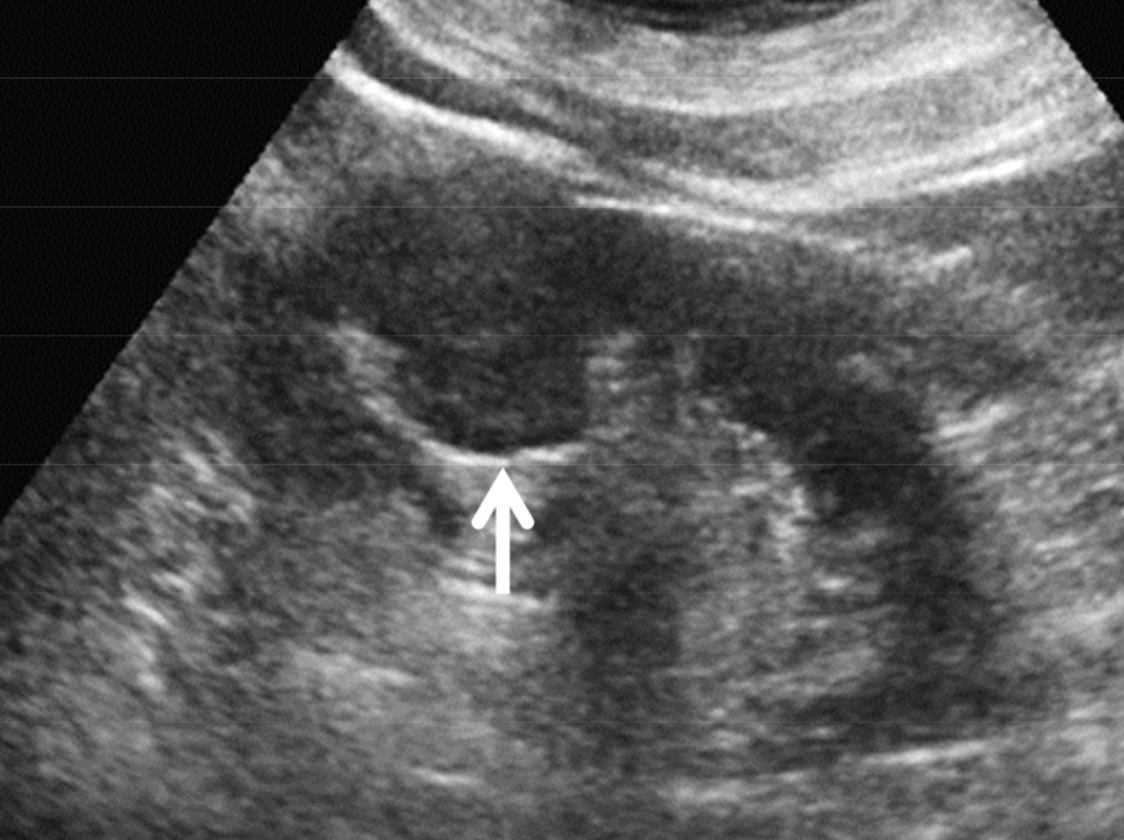

신장 석회화 진단 및 검사 방법은?

신장 석회화를 진단하는 방법은 여러 가지가 있습니다. 혈액 검사는 신장 기능을 평가하고 혈중 칼슘 및 인 수치를 확인하는데 사용됩니다. 또한 요액 검사, 초음파, CT, MRI 등의 영상 진단도 신장 내 석회화를 확인하는 데 도움이 됩니다.